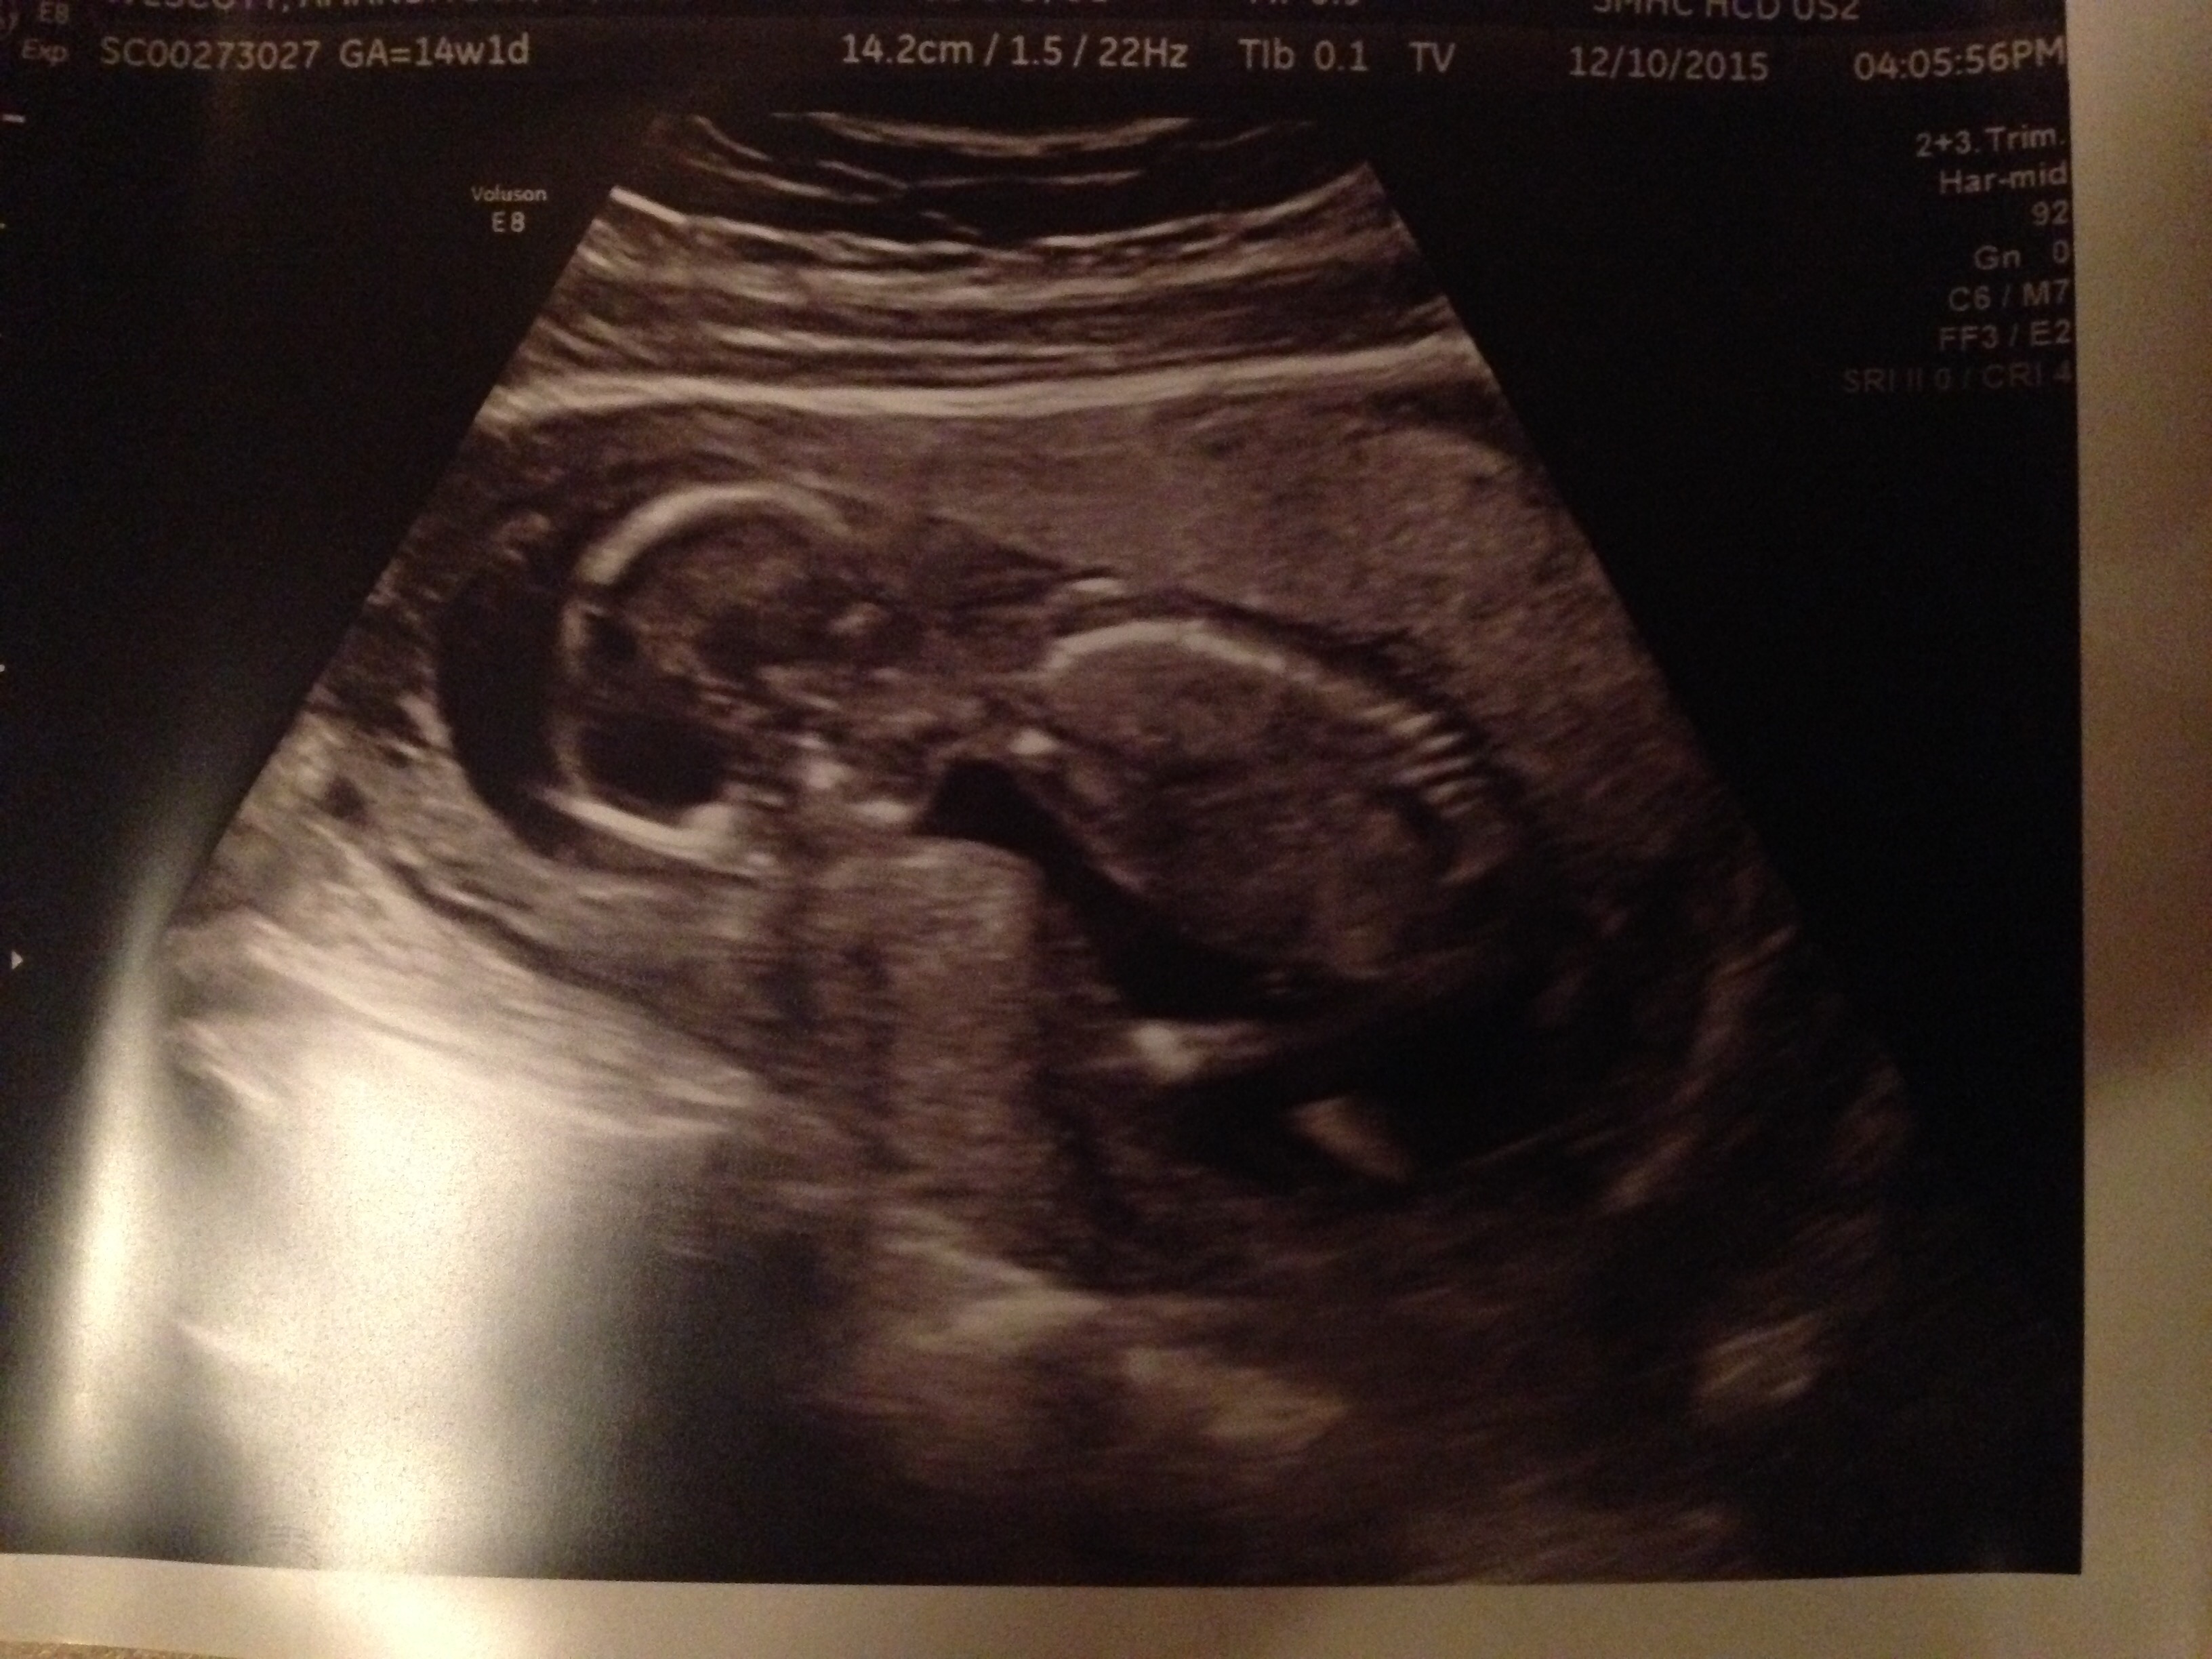

14 weeks 1 day. My Dr at my exam last week thought I felt further along, so we had this as a dating ultrasound and I was right. So happy I got to see baby!

Had unscheduled ultrasound due to unexplained bleeding. Still don't know why I'm spotting (grr) but both babies were okay. 14+4 at the time of the scan. Baby A refused to face the camera.